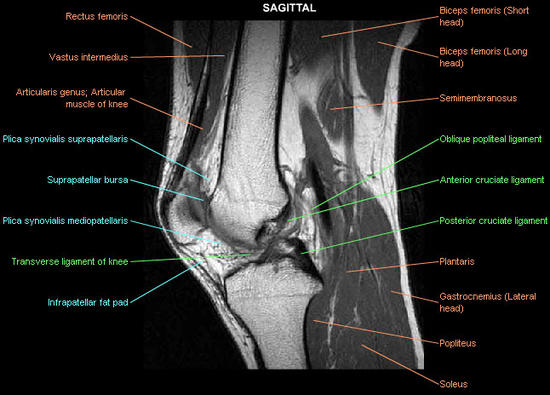

knee-cruciate-ligament_imagelarge Home | Injection Therapy | Prolotherapy | knee-cruciate-ligament_imagelarge